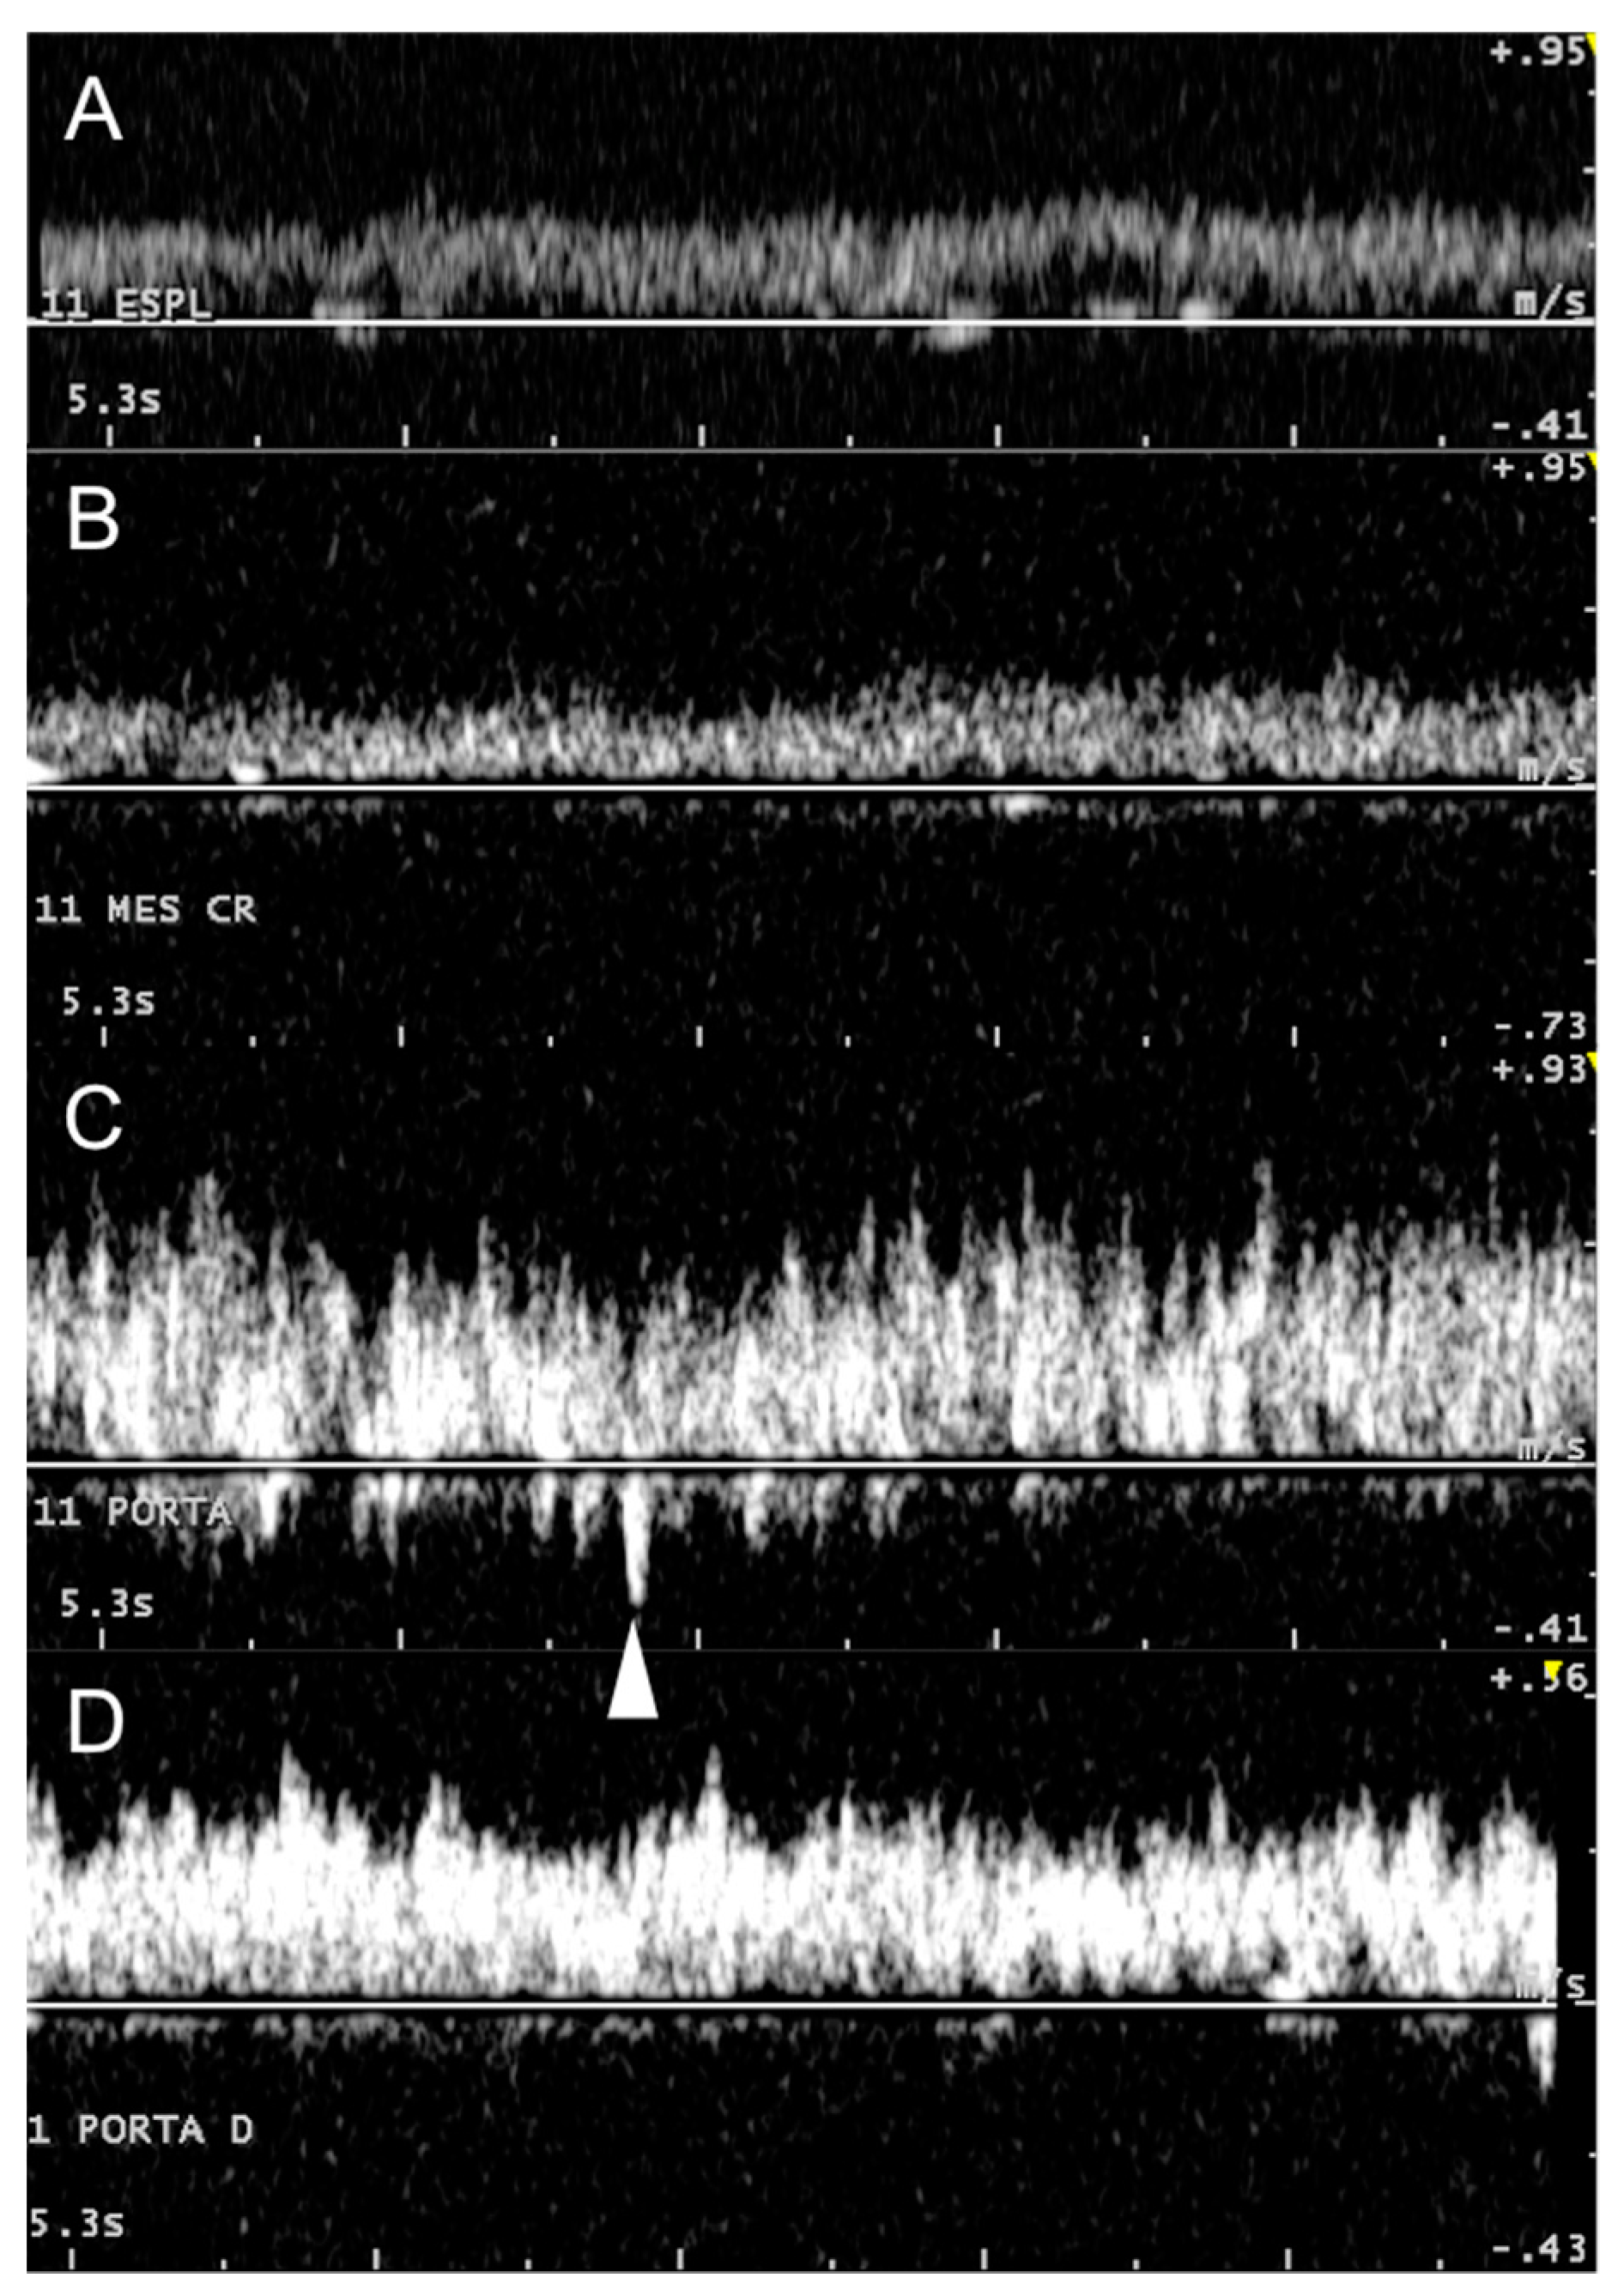

3.2. Portal System

3.3. Caudal Vena Cava and Hepatic Veins